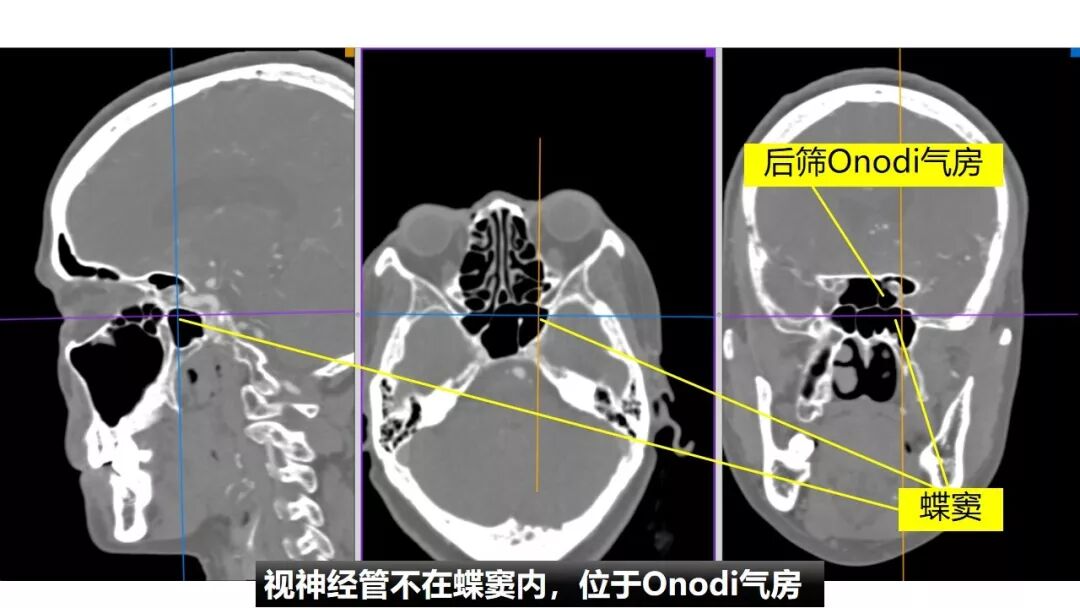

Osirix冠矢轴